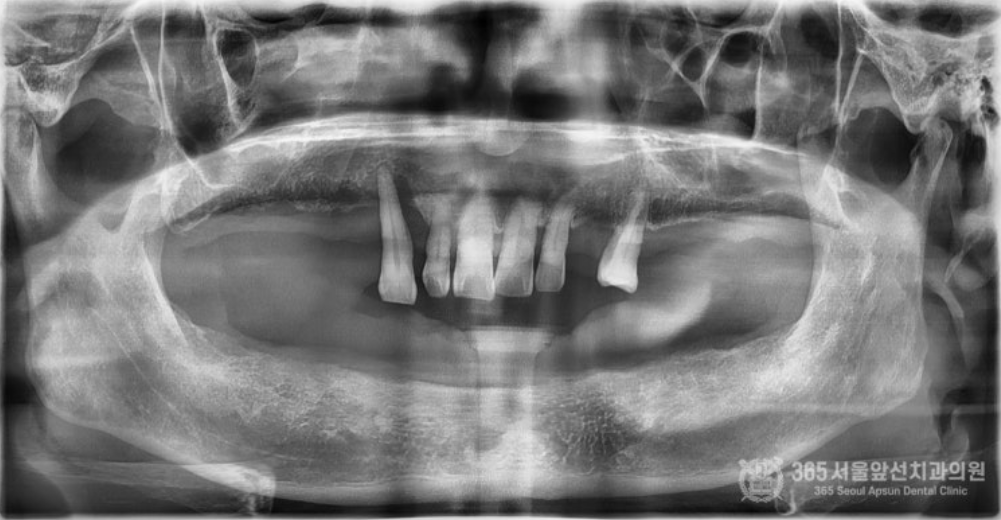

통증이 두려워서 무절개로 수술을 하고 싶어요. 무절개 임플란트 수술을 문의 주셨던 환자분입니다. 윗턱에는 불편하지만 사용하시던 틀니가 있기에, 일단은 아랫턱만 임플란트 수술을 원하셨습니다. 촬영일시 : 2024.05.14. 초진 내원 당시 구강내 엑스레이 사진입니다. 보시다시피 아랫턱은 완전 무치악으로 치아가 전혀없습니다. 무절개 방식을 사용하여군더더기 손 동작 없이 정확하고 빠르게 15분만에 수술을 마무리 해드렸습니다ㅎㅎ 충분한 숙련도를 갖춘 의료진이라면 불필요한 디지털 가이드 방식의 수술이나 복잡하고 번거로운 도구없이 감각만으로 빠르고 정확한 수술이 가능합니다. 지금까지 만 개 이상의 임플란트를 식립해오면서 얻게 된 수술 경험으로 불필요한 과정없이 필요한 술식만으로 임플란트 수술을 진행하고 있습니다. 촬영일시 : 2024.05.14. 수술 직후 3차원 CT입니다. 정확한 위치에 올바른 각도와 간격으로 임플란트들이 가지런히 식립되어있습니다. 촬영일시 : 2024.08.22. 4개월 후 완성 후 사진입니다. 지금까지 365일 늘 가까운 서울대학교 치과병원을 지향하는, 365서울앞선치과 강동우 대표원장이었습니다! 앞으로도 도움이 되는 증례로 찾아뵙겠습니다. 감사합니다. [ 치료기간: 2024년 5월14일 ~2025년 8월 22일 )] |